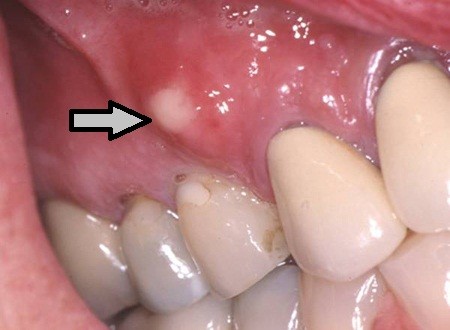

Diş köklerinde apse varlığında çekim tek seçenek değildir. Önce kanal tedavisi yapılır. Yeterli olmazsa da rezeksiyon şansı vardır.

Apikal rezeksiyon, inatçı kök apselerinde diş köküne dışarıdan yapılan direk müdahale ile tedavi sağlanmasıdır.

Dişin kökünün ve apsenin olduğu bölgede çene kemiği üzerinden küçük bir pencere açılır, apse temizlenir. Diş iyileşmeye bırakılır.

Kökteki lezyonun büyüklüğüne, dişin kökünün harabiyet derecesine göre sadece kök ucu bölgesinden veya diş ile diş etinin başladığı sınırdan itibaren kemik yüzeyi açılır, kök ucundaki iltihabi doku temizlenir. Burada bakterilerin tam olarak yok edilebilmesi açısından diş kökünün bir kısmında da kesi yapılacaktır.